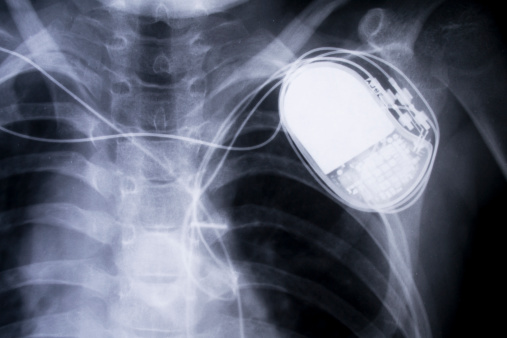

TORONTO — Deux cabinets d’avocats veulent intenter une action collective nationale contre les fabricants de défibrillateurs cardiaques internes qui pourraient s’arrêter à tout moment, sans prévenir, à cause d’une défectuosité des piles.

Environ 8000 Canadiens sont porteurs de défibrillateurs cardiaques de marques Fortify, Fortify Assura, Fortify Assura MP, Unify, Unify Assura ou Unify Quadra fabriqués entre janvier 2010 et le 23 mai 2015. Les appareils fabriqués après cette date ne sont pas visés.

Santé Canada et la FDA américaine avaient émis l’an dernier des avis de sécurité concernant les appareils de St.Jude Medical, qui doivent en théorie surveiller la fréquence cardiaque et donner au coeur une thérapie, sous forme de petites impulsions électriques. Ces défibrillateurs devaient durer au moins sept ans avant d’être remplacés.